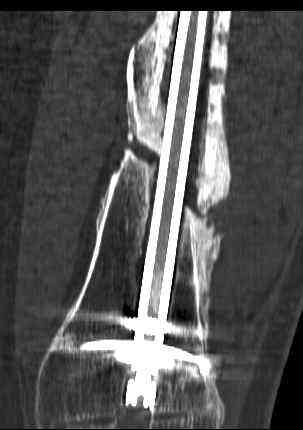

july 05: LISS femur, LCP plate tibia, double recon. plate post. acetabulum

oct 05: cancellous bone graft femur

aug 06: blade plate + bone graft

nov 06: revision blade plate

feb 07: retrograde nail + bone graft + BMP

may 07: dynamisation nail

sept 07: locking screw removal (max. dynamisation reached)

nov 07: persistant non-union distal femur; other fractures healed

uneventfully.